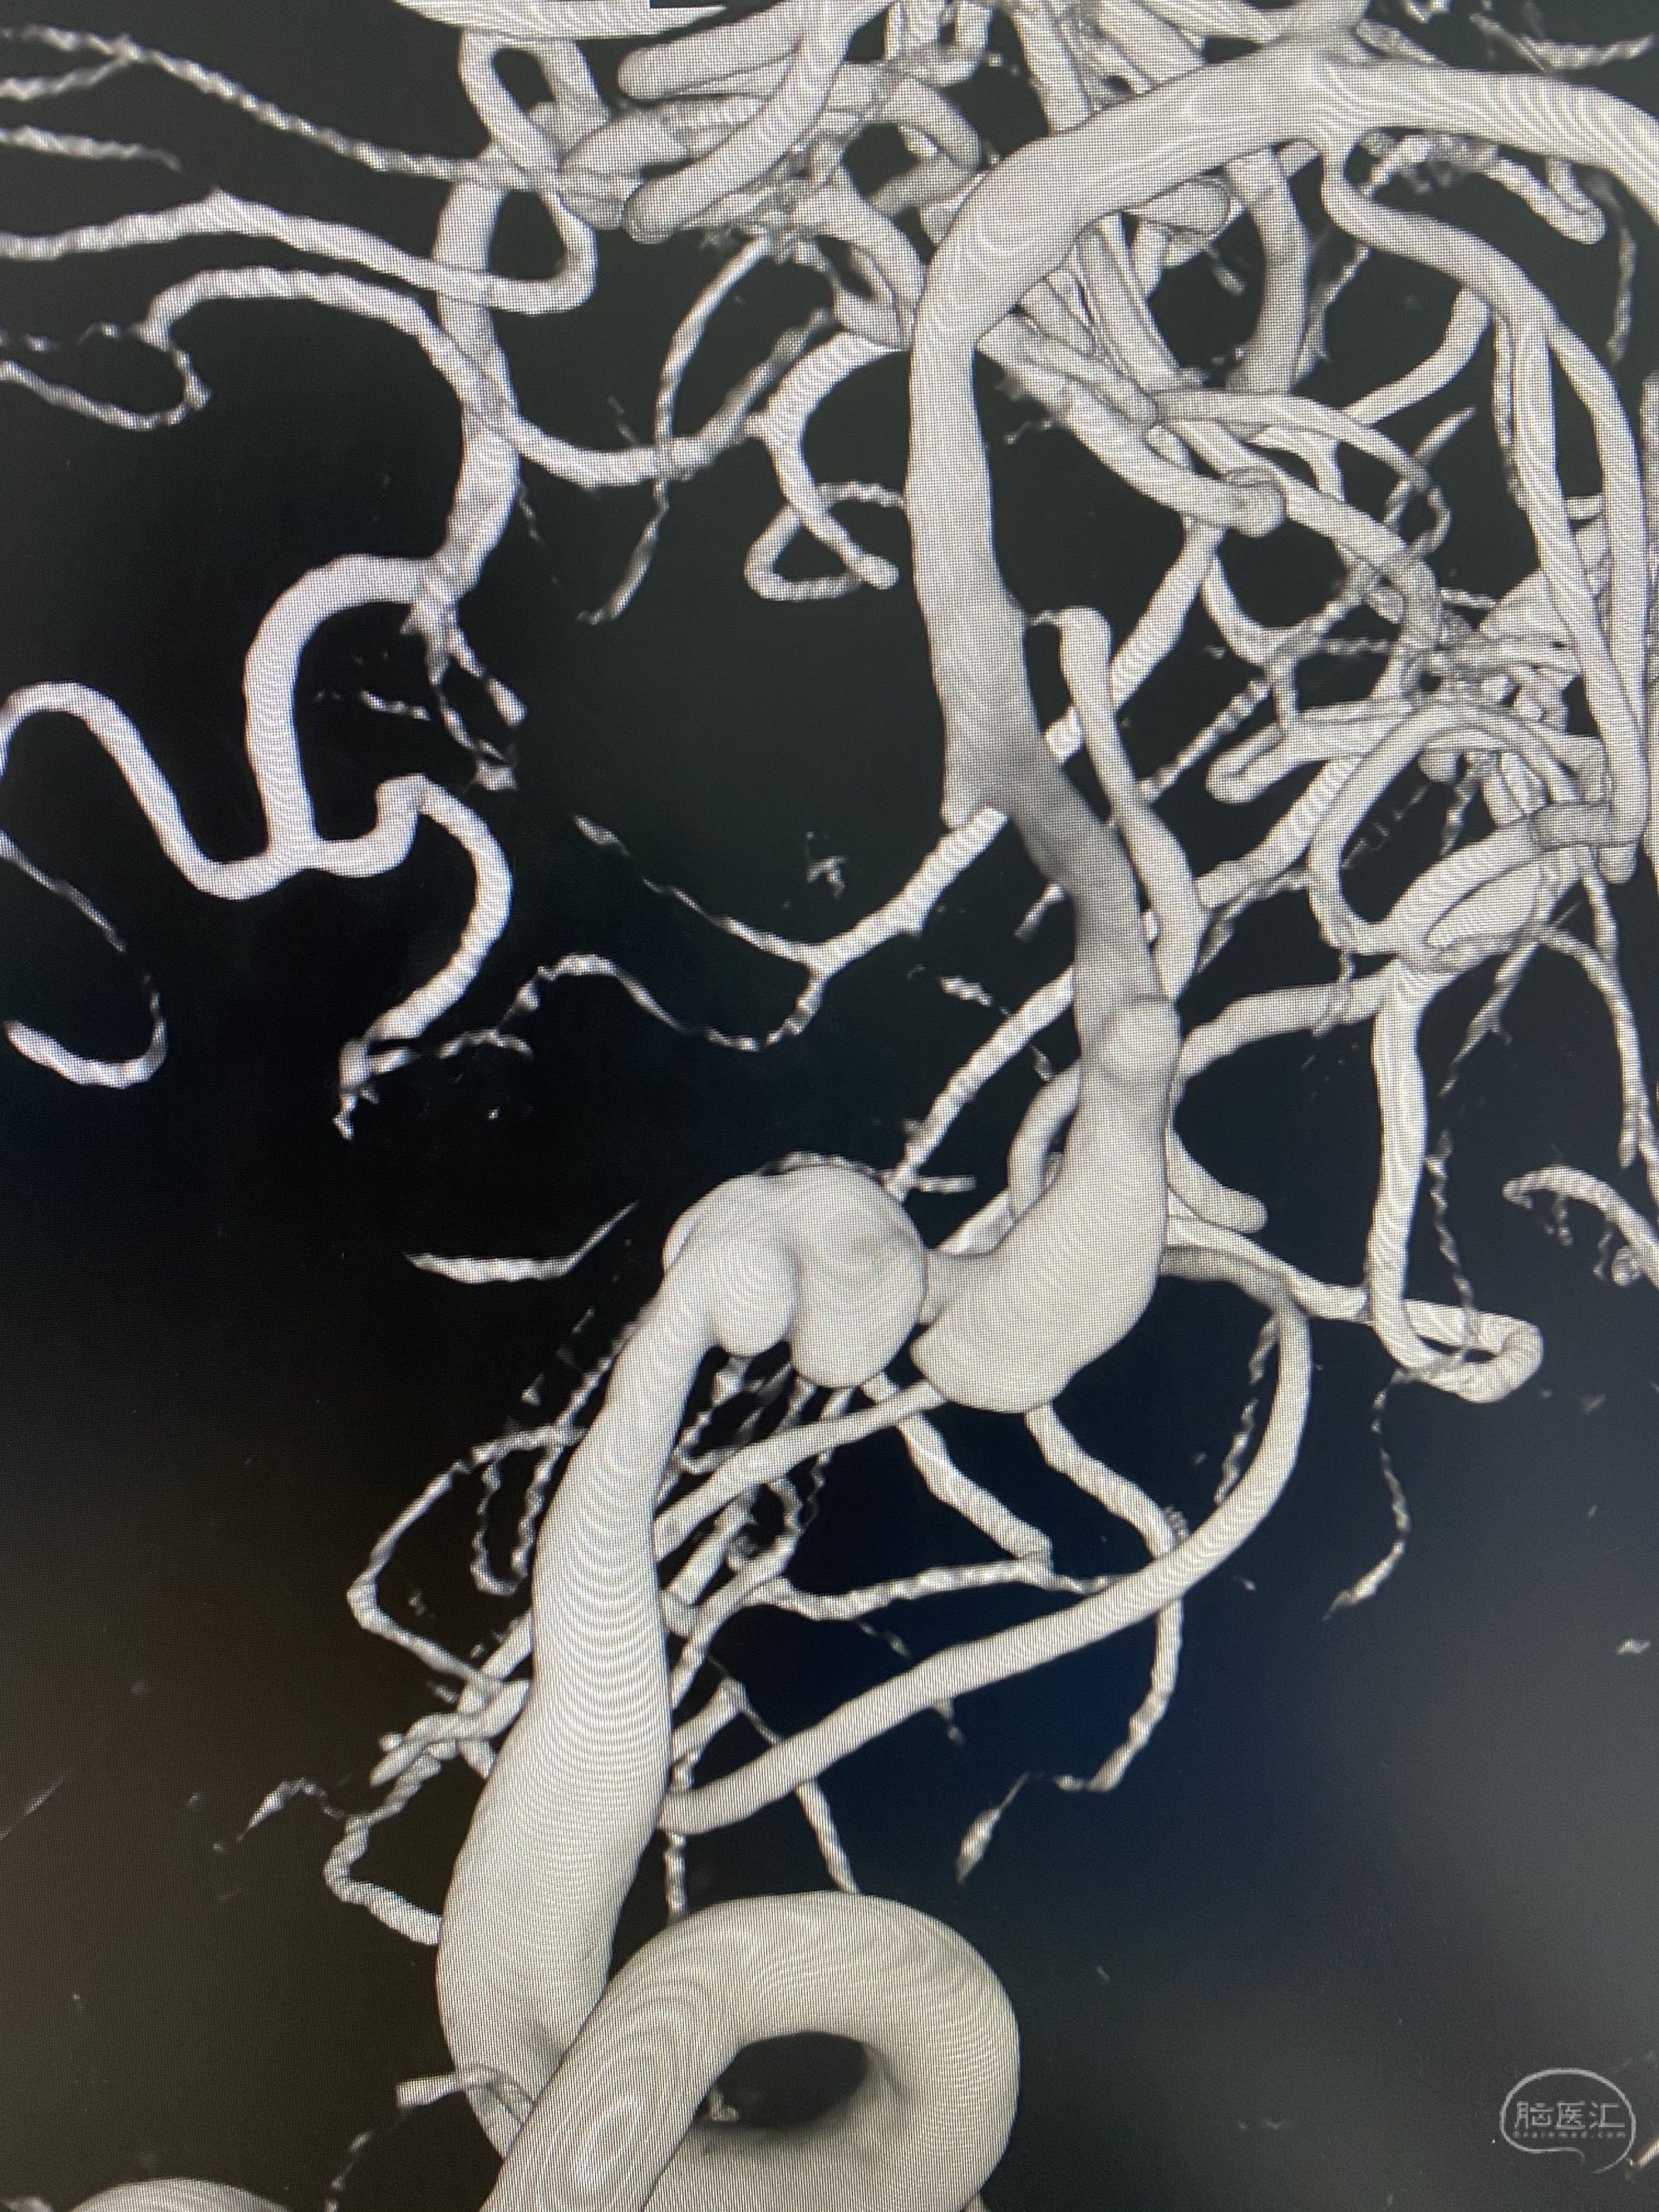

椎动脉颅内段多发夹层动脉瘤伴载瘤动脉狭窄pipeline flex植入

今日手术,TJG,M62Y,一期左侧颈动脉狭窄支架植入,二期椎动脉V4段多发夹层动脉瘤伴狭窄,常规支架辅助栓塞方法复杂又危险,血流导向装置植入快捷又安全。南阳市中心医院神经内科脑血管病介入团队pipeline flexFD植入两人导师资格。